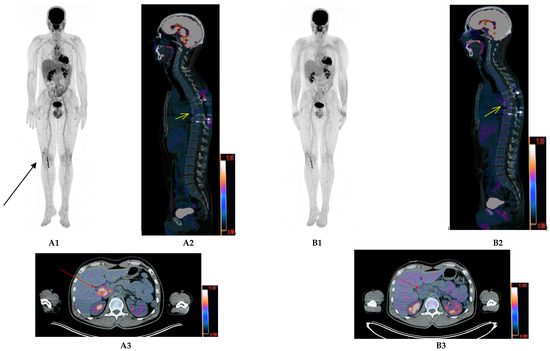

- Rasche, L.; Alapat, D.; Kumar, M.; Gershner, G.; McDonald, J.; Wardell, C.P.; Samant, R.; van Hemert, R.; Epstein, J.; Williams, A.F.; et al. Combination of flow cytometry and functional imaging for monitoring of residual disease in myeloma. Leukemia 2019, 33, 1713–1722. [Google Scholar] [CrossRef] [PubMed]